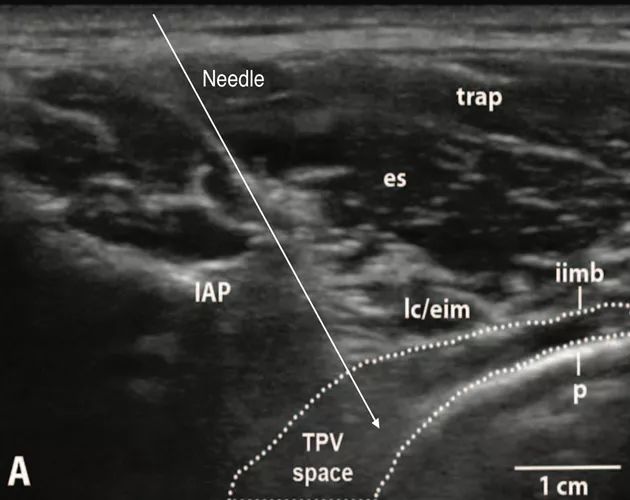

a.入路④(IAP内向平面内入路),其超声影像及相关解剖如下[2]:

(TPV space:胸椎旁间隙,IAP:下关节突,iimb:肋间内膜,SCTL:上位肋横突韧带,p:壁层胸膜,es:竖脊肌,trap:斜方肌,lc/eim:肋提肌/肋间外肌,ST:交感干。Anesthesiology 2015; 123:459-74)